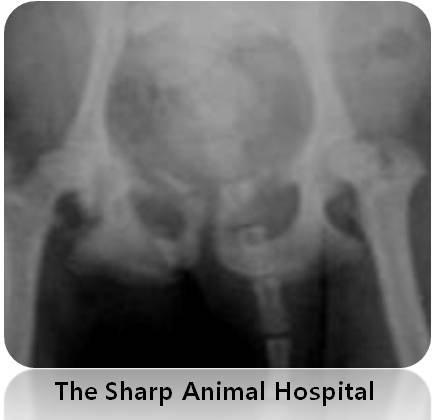

그런데 정작 문제는 골반골에 있었습니다.

골반골에 골절이 있었어요..

조금 확대 해서 보면 뿌러지 뼈 조각들이 나뉘어져 있는 것을 확인 하실 수 있습니다. ( 노란색 화살표 )